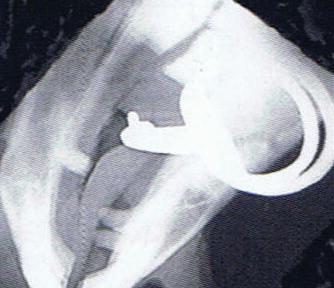

Here is a veterinary radiographic report on a horse with a fracture evident on the medial toe and after treatment and feeding Bone Gold during this period. More information on these products can be found at www.vetgold.com.au

XXXXXXX's left and right front feet were radiographed on 26th Aug, 21st Oct (8 weeks) and again on the 17th Nov '21(12 weeks).

XXXXXXX’s left and right front feet were radiographed on 26th Aug, 21st Oct (8 weeks) and again on the 17th Nov ‘21(12 weeks).

26.08.21: Right Front: Large P3 solar margin fracture evident on medial toe 32.6mm x 4.1mm with approximately 1.4mm separation from parent bone as below left image.

21.10.21: Right Front: Fine residual 4.2mm fracture still evident, approximately 90% resolution

17.11.21: Right Front: Fracture fully resolved

26TH AUG 21

21ST OCT 21

Radiographic results as of the 17th Nov '21 show total resolution of the original fracture.

XXXXXXX was reshod today utilising off an alloy shoe with a toe clip - inner circumference seated out to avoid any sole pressure. The horse can return to training.

Solar margin Type IV fractures of this magnitude have well-documented internationally published healing rates of 7 - 12 months. Full resolution of these fractures is rare as most often the fracture fragments are resorbed. Full resolution in a 3 month period was not anticipated.

The horse was on Bone Gold 3 x scoops fed once per day for this period.